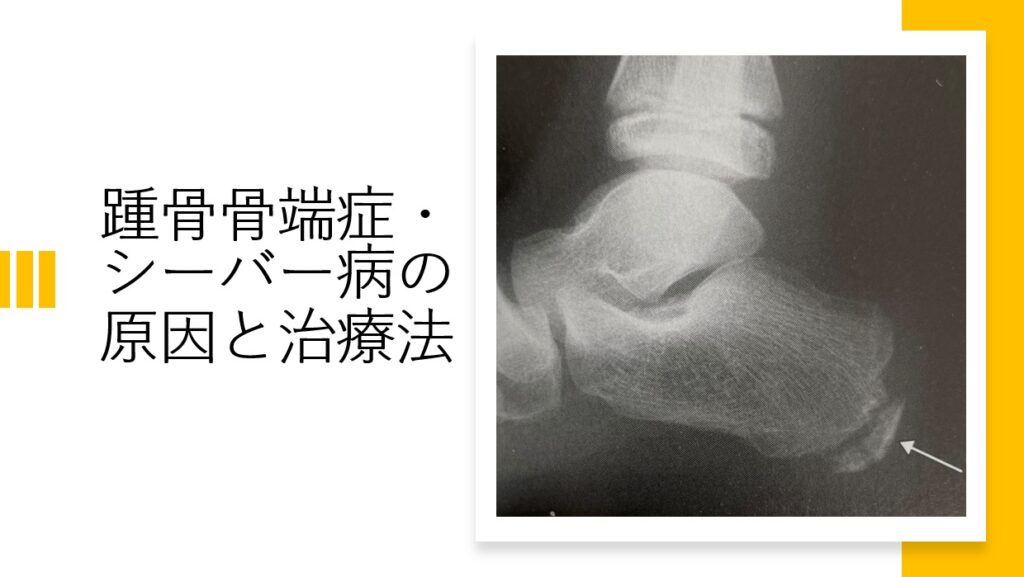

51fhOfp+BwL.jpg_BO30,255,255,。12229096c1fb86efb040ed7b051c87。骨盤・股関節・鼠径部のスポーツ疾患治療の科学的基礎 (Sports。下記シリーズの①〜⑨ 9冊セット「下肢のスポーツ疾患治療の科学的基礎 筋・腱・骨・骨膜」福林 徹 / 蒲田 和芳 / 金岡 恒治定価: ¥ 3000外側は、綺麗なものと焼けや多少の汚れがあるものがあります。画像をご参照ください。中身は綺麗で状態も良いと思います。特に書き込み等ありません。#福林徹 #福林_徹 #蒲田和芳 #蒲田_和芳 #金岡恒治 #金岡_恒治 #本 #自然/医療・薬学・健康。踵骨骨端症(シーバー病・セーバー病)の原因と治療法 - HK LABO。米穀データバンク 米マップ 14-21 8冊 セット まとめ。TRPG サタスペ 全巻セット+リプレイ。忍たま乱太郎アニメーションブック 忍たま忍法帖 設定資料集

• 踵骨骨端症(シーバー病・セーバー病)の原因と治療法 - HK LABO